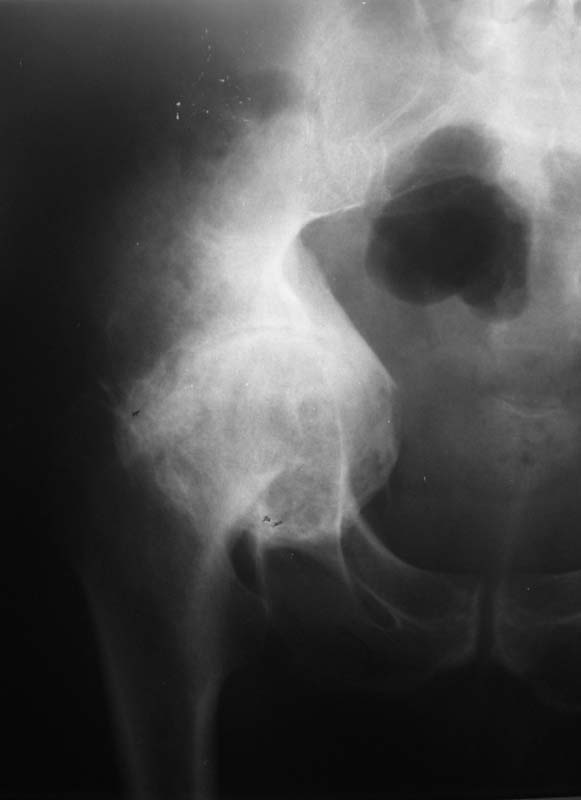

Мужчина, 54 г. В 12 лет перенес травму правого тазоберенного сустава.

Клинически движений в суставе нет, хотя при ходьбе беспокоят боли.

Предполагаем имплантацию <чашки> протеза в сформированное ложе без удаления головки бедра.

Ваше решение абсолютно адекватное и возражений нет, но проблема будет не в этом. У Вас будут сложности в 1) правильной ориентации чашки относительно истинной вертлужной впадины и 2) создании необходимого

"оффсета", попросту говоря, будет крайне сложно "оторвать" бедро от таза. Для этого мы в своей практике пользуемся расширенным передним и задним релизом, как правило, на это уходит достаточно много времени.

Может возникнуть ещё одна проблема, но после без сомнения успешной операции.Р-гр.картинка будет красивой, а вот движения в оперированном тазобедренном суставе после длительного анкилозирования т/б сустава могут не восстановится. В основном за счёт атрофии мышц.Только боли пройдут. И об этом больной должен знать заранее.С уважением

У нас был случай несколько похожий. У больного сформировался анкилоз в возрасте 4-5лет. После операции эндопротезирование, рентгенологическая картина была нормальной. Пассивный объем движений:сгибание-90-95,разгибание- 170, отведение-15. Проблемы возникли с активными движениями и опороспособностью конечности. Из-за значительной атрофии и жирового перерождения мышц, больной не смог пользоваться конечностью. Спонтанно возникала внутренняя или наружная ротация в зависимости от положения. Больному пришлось наложить кокситную гипсовую повязку, после чего он смог ходить с опорой на ногу.Необходимо учитывать возраст, в котором образовался анкилоз или выраженная контрактура,т.к. от этого зависит функциональный исход операции.

Безусловно будут большие технические проблемы с отделением бедра от таза. Ложе для чашки (кстати, какого типа?)придется формировать с нуля. Восстановить длину конечности - тоже проблема, учитывая атрофию окружающих мыщц. Кстати, каково укорочение конечности? В общем, можно получить весь букет технических трудностей протезирования и при этом не получить ни одного его преимущества... Мне кажется, это случай для артродеза.